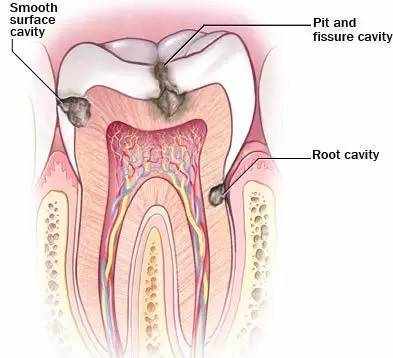

龋齿是口腔最常见的疾病之一,俗称蛀牙,更加通俗的描述就是在牙齿上出现了小洞、大洞,甚至大面积的牙体缺损。

龋齿的发展

白斑

牙垢沉积在牙齿表面,牙齿表面珐琅质被牙垢中的细菌消化糖后,排泄出来的酸溶解,就发生脱矿了。

牙齿中的钙减少了,色泽就变成白粉笔色(白琧)感觉了。

釉质龋

脱矿没有及时修复,牙齿表面开始缺损,就成为我们说的蛀牙、牙洞了。

牙本质或牙骨质龋

随着龋坏的发展,逐渐出现喝冷热水或者进食时敏感不适。

深龋

此时如果不及时治疗龋坏,将继续向深层牙体组织发展,就会出现遇冷遇热疼痛,之后形成明显龋洞。

当有食物进入龋洞后常导致患牙疼痛,此时已发展为深龋,换言之,龋洞已经很深,洞底与牙神经之间的距离已经非常近。